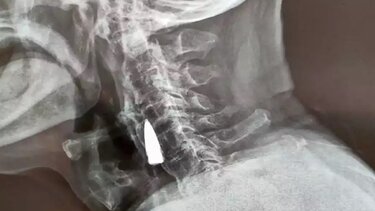

Οι γιατροί αφού του έκαναν ακτινογραφία για να βεβαιωθούν ότι δεν είχε υποστεί σοβαρή βλάβη στον αυχένα του βρέθηκαν μπροστά σε ένα απίστευτο θέαμα καθώς βρήκαν ένα ξένο αντικείμενο στο λαιμό του, το οποίο αργότερα κατάλαβαν ότι ήταν ....σφαίρα.

Ο ίδιος ο 95χρονος πάντως εκτιμά ότι η σφαίρα βρίσκεται στο λαιμό του από το 1944 (!) όταν χτυπήθηκε από σφαίρα ενώ διέσχιζε ένα ποτάμι. Η σφαίρα φέρεται να μπήκε μέσα από την αριστερή πλευρά της μύτης, διαπέρασε την άνω γνάθο του και του έβγαλε ένα από τα δόντια του πριν σφηνωθεί στο λαιμό του.